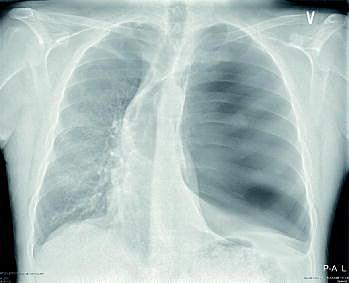

En 48-årig mand fik under udredning i forbindelse med lungesygdom taget et røntgenbillede af thorax. Billedet blev tolket som visende venstresidig tryk-pneumothorax med overskydning af mediastinum mod højre. Den kirurgiske bagvagt blev kontaktet med henblik på anlæggelse af pleuradræn.

Lægen hastede til stuen på grund af trykpneumothorax, men fandt patienten upåvirket med normale værdier og 2 l ilt på dobbeltløbet næsekateter. Patienten oplyste, at han havde cyster på venstre lunge (vanishing lung disease ), fik hjemmeilt og var i sin respiratoriske normaltilstand.

På grund af diskrepans mellem de radiologiske og de kliniske fund blev røntgenafdelingen kontak-tet. Tidligere udført computertomografi og røntgenoptagelse af thorax blev gjort tilgængelige, og man kunne konstatere, at patienten allerede ni måneder tidligere havde en stor bulla, der udgik fra venstre lunges overlap og var årsag til den mediastinale forskydning.

Det viste røntgenbillede adskiller sig fra et billede af en trykpneumothorax ved: 1) fravær af sammenklappet lunge ved hilus, 2) medialt beliggende strøg af lungeparenkymet apikalt og basalt og 3) at diafragma ikke står skarpt på grund af en atelektatisk venstre underlap.

Anlæggelse af pleuradræn eller akut dekompression ville hos denne patient sandsynligvis have punkteret lungecysten og medført akut respiratorisk forværring.

Patienten fik på et senere tidspunkt foretaget bullektomi med god effekt på både lungefunktionen og funktionsniveauet.